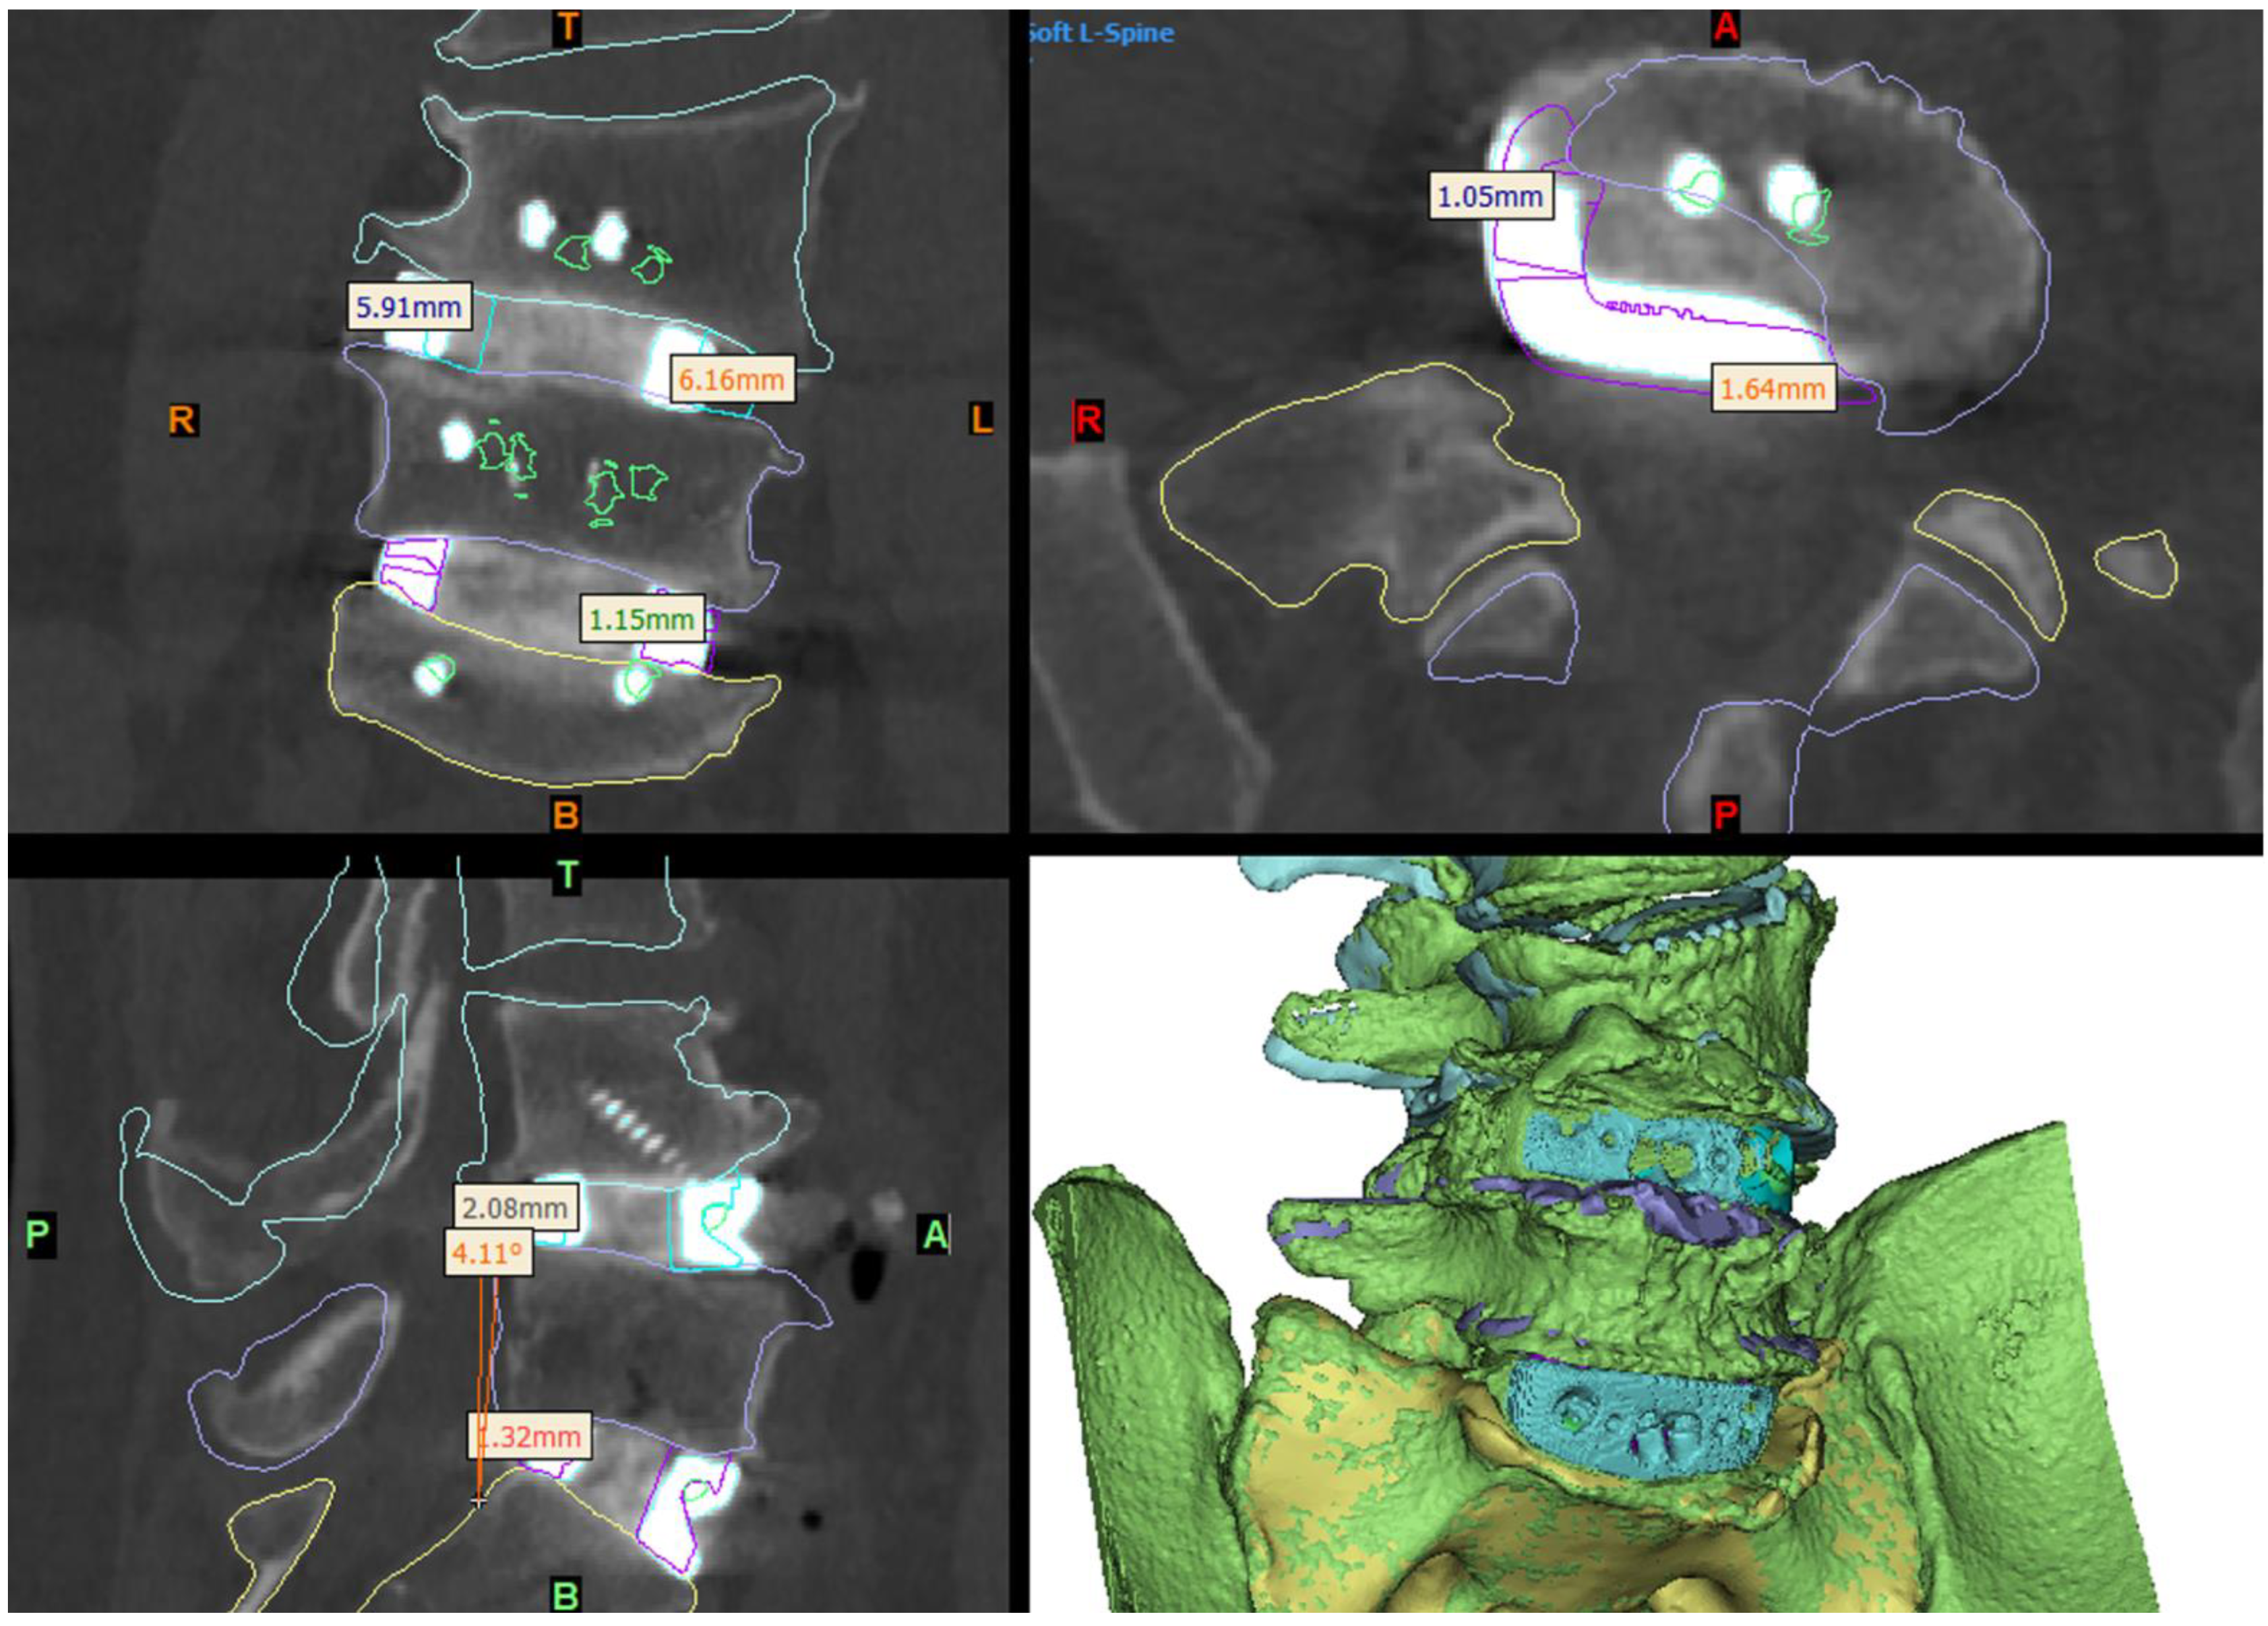

Imaging at day 1 postoperatively demonstrated excellent implant positioning (Figure 6). Disc and neuroforaminal height correction, as well as lordotic and partial scoliotic correction closely matched the planned correction in the VSP. At 9-month postoperative imaging, implant positioning and parameter corrections were stable. Early radiographic evidence of bony fusion at both operative levels and osteophyte resorption were appreciable (Figure 7).

Figure 6.

Day-1 postoperative CT and 3D reconstruction of the construct (bottom right panel) compared to the virtual surgery planned (VSP) device and anatomy positioning (shown by the coloured outlines). The L5-S1 device was positioned very close to the VSP position, being ~1–1.5 mm further to the right and anterior than planned. The L4-L5 device was implanted ~6 mm to the left and ~2 mm anterior to the VSP position (see Section 3), which resulted in slightly less coronal and a sagittal-plane angle adjustment of the L4 hemivertebra being achieved than planned.

The close adherence of the relative implant and anatomy positioning in postoperative imaging to the preoperative VSP demonstrates the accurate realisation of VSP correction goals and the validity of this technique (Figure 6). The ability to assess the vascular anatomy preoperatively and refer to the VSP intraoperatively allowed the surgical team to be better prepared, particularly in dealing with the extensive adhesions at the aortic bifurcation, and more rapidly successfully manage the intraoperative aortic tear [8]. The use of prominent osteophytes as patient-specific pathoanatomical landmarks also aided surgical navigation.